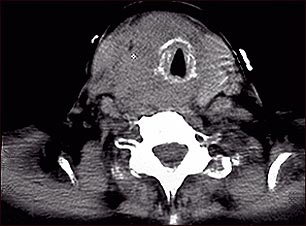

Tomografía computarizada de cáncer de tiroides

Tomografía computarizada de un tumor en la garganta, consecuencia de un cáncer tiroideo. Este tumor ha rodeado, constreñido y desplazado la tráquea.